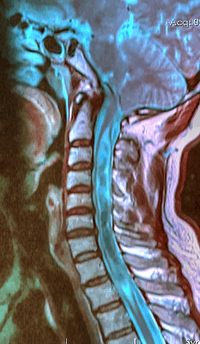

A sagittal FLAIR MRI scan, from a patient with an Arnold-Chiari malformation, demonstrating tonsillar herniation of 7 mm | |

Diagnosis is made through a combination of patient history, neurological examination, and medical imaging.[12] Magnetic resonance imaging (MRI) is considered the best imaging modality for Chiari malformation since it visualizes neural tissue such as the cerebellar tonsils and spinal cord as well as bone and other soft tissues. CT and CT myelography are other options and were used prior to advent of MRI, however they characterize syringomyelia and other neural abnormalities less well.

By convention the cerebellar tonsil position is measured relative to the basion-opisthion line, using sagittal T1 MRI images or sagittal CT images.[13] The selected cutoff distance for abnormal tonsil position is somewhat arbitrary since not everyone will be symptomatic at a certain amount of tonsil displacement, and the probability of symptoms and syrinx increases with greater displacement, however greater than 5 mm is the most frequently cited cutoff number, though some consider 3–5 mm to be "borderline," and symptoms and syrinx may occur above that.[13][14][15] One study showed little difference in cerebellar tonsil position between standard recumbent MRI and upright MRI for patients without a history of whiplash injury.[11] Neuroradiological investigation is used to first rule out any intracranial condition that could be responsible for tonsillar herniation. Neuroradiological diagnostics evaluate the severity of crowding of the neural structures within the posterior cranial fossa and their impact on the foramen magnum. Chiari 1.5 is a term used when both brainstem and tonsillar herniation through the foramen magnum are present.[16]